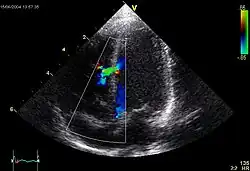

Echocardiographic image of a moderate ventricular septal defect in the mid-muscular part of the septum. The trace in the lower left shows the flow during one complete cardiac cycle and the red mark the time in the cardiac cycle that the image was captured. Colours are used to represent the velocity of the blood. Flow is from the left ventricle (right on image) to the right ventricle (left on image). The size and position is typical for a VSD in the newborn period.